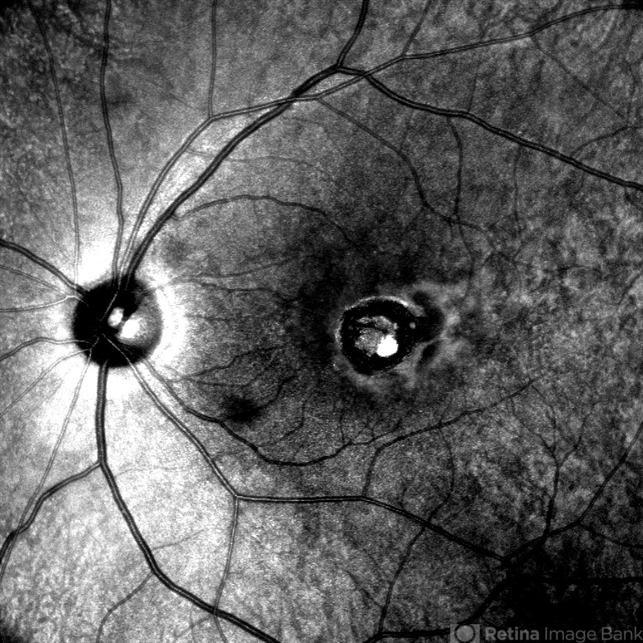

- macular coloboma

Scanning laser ophthalmoscope

MIRANTE - Description

- Infrared fundus image of the LE of a 32 year-old male showing macular coloboma.